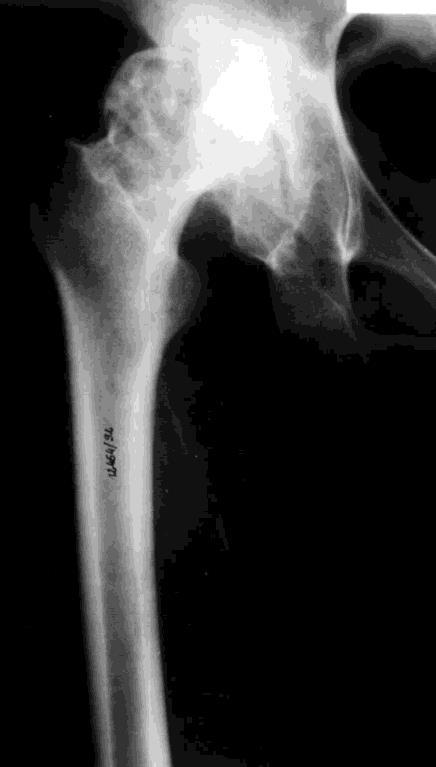

Jaki typ zmian zwyrodnieniowych stawu biodrowego przedstawia radiogram?